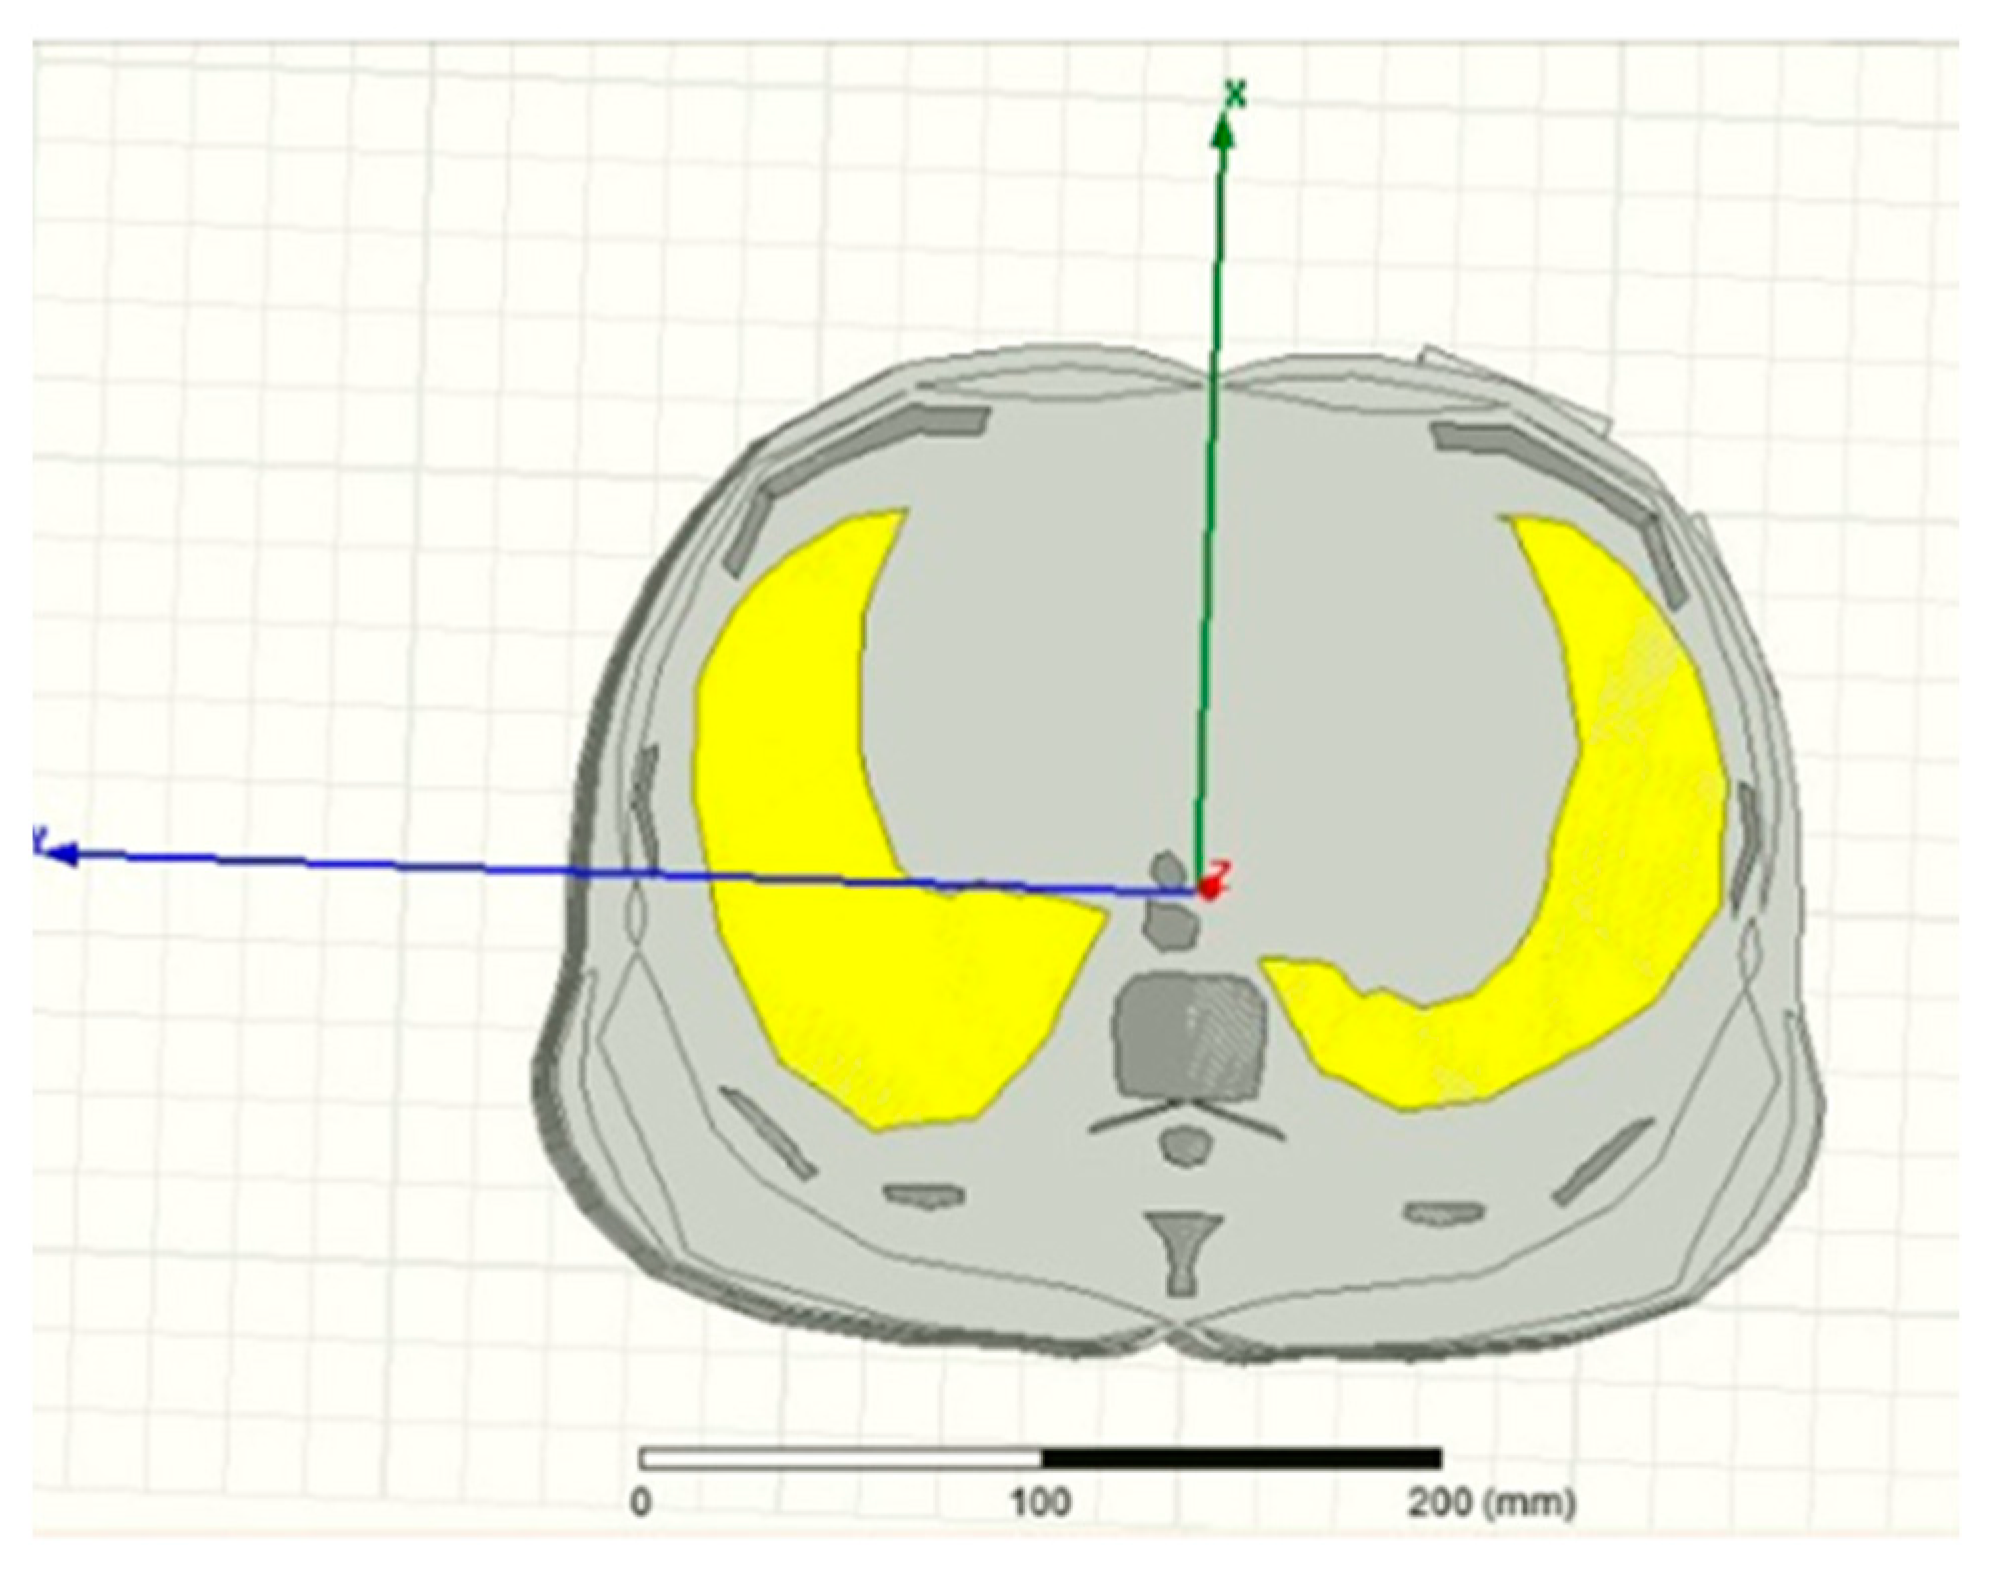

- Leong, C.; Xiao, Z.; Yun, Z.; Iskander, M.F.I. Non-Invasive assessment of lung water content using chest patch RF sensors: A computer study using NIH patients CT scan database and AI classification algorithms. IEEE Access 2023, 11, 13058–13066. [Google Scholar] [CrossRef]

- Abd El-Hameed, A.S.; Elsheakh, D.M.; Elashry, G.M.; Abdallah, E.A. A Comparative Study of Narrow/Ultra-Wideband Microwave Sensors for the Continuous Monitoring of Vital Signs and Lung Water Level. Sensors 2024, 24, 1658. [Google Scholar] [CrossRef] [PubMed]